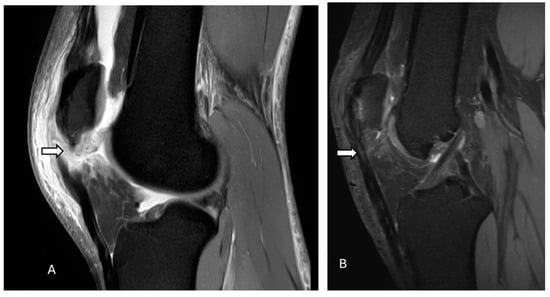

3.1. Acute Patellar Subluxation and Dislocation